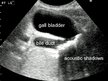

Ultrasonogrāfija